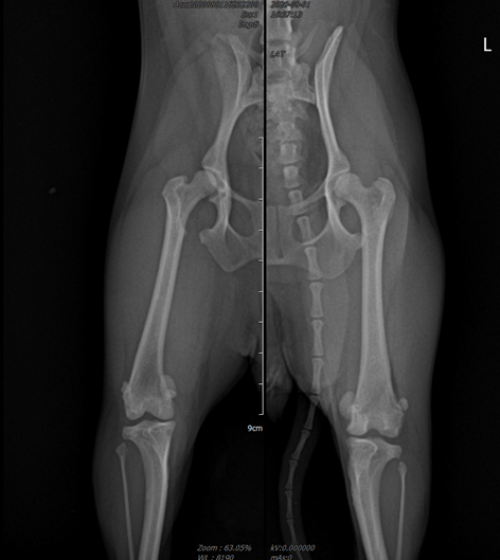

올바른 예시: 허벅지뼈가 정면을 정확히 응시하도록 촬영되어, 뼈의 변형 정도와 수술 위치를 정밀하게 파악